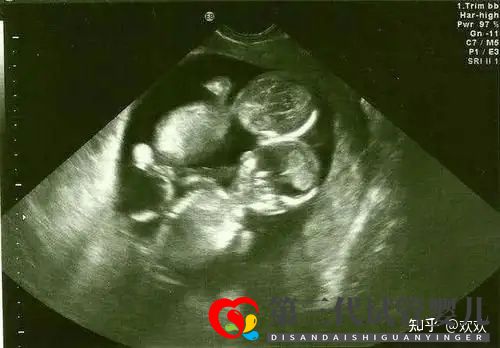

然后就是我再次来到了深圳进行移植了,移植过程是完全不痛的,在我印象里好像只有5分钟吧,移植后医生让我平躺休息了将近2个半小时,也是根据我要求的,移植的双胎,这次也是在这边待了将近小半个月的,验孕后才回家的,那个时候还不知道是不是两个胚胎都着床了,到7周+B超,这个时刻我真的是刻骨铭心!听到医生说,2个宝宝都有心跳的那一刻,我又激动又感动!保佑后面都一路顺顺利利!宝宝健健康康的成长,可能是双胎的原因现在的孕肚已经非常的明显了,我还特意买了胎心检测仪,平时总听两个宝贝的心跳生,希望我这一次双胎N宝的好孕也能传递给您。